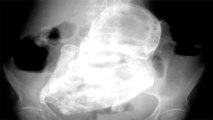

Doctors Discover 40 Year Old Fetus Inside 82 Year Old Woman

81-year-old Brazilian woman dies after doctors remove a 56-year-old 'stone baby' from her body